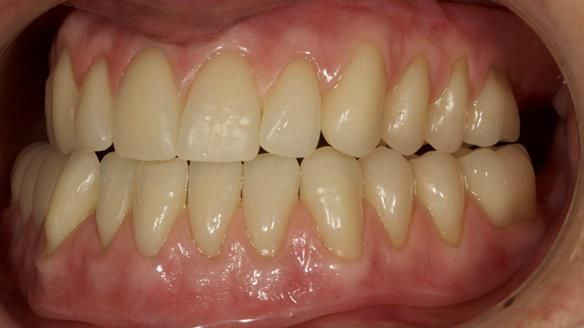

This newsletter describes in step by step detail the provision of a lower implant supported metal based complete denture with three dental implants positioned in the anterior mandible. The upper arch was restored with a metal based complete upper denture.

Mary had 3 dental implants placed in the anterior mandible 10 years previously with new complete dentures. These were successful for a time. The dentures were replaced a few years later. Mary was never pleased with the new lower denture as they did not fit the implants properly. This patient was referred to me from Ireland, to my practice in Garstang, England.

Diagnoses of the complete dentures

- Locator attachments not engaging the housings in the lower denture.

- Suboptimally shaped dentures with poor tissue fit resulting in rocking of the dentures.

- Bland aesthetics.